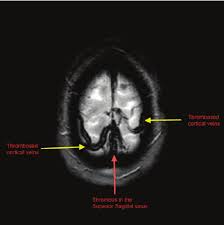

For this reason, it seems to be overlooked not only by general practitioners but also in some specific cases by neurologists as well.1. Cerebral venous sinus thrombosis occurs when a blood clot forms in the brain's venous sinuses. Cerebral venous sinus thrombosis (cvst) is less common than other types of stroke but can be more challenging to diagnose due to its varied presentation patterns; The most frequent and often early symptom of thrombosis of cerebral veins and sinuses is a headache. H u h n a. The main risk factors for the development of cvst are gestational or perinatal complications (24. Although, the frequency of cerebral venous sinus thrombosis (cvst) has dropped remarkably in recent years but unfortunately, it is still seen commonly in a developing country like pakistan. Die thrombosen der intrakraniellen venen und sinus, stuttgart, 1965;

Cerebral venous sinus thrombosis occurs when a blood clot forms in the brain's venous sinuses. The diagnosis of cvst needs high threshold for suspicion, especially in patients with meningitis or. Prognosis of cerebral vein and dural sinus thrombosis: You may also need to take part in a special rehab program or physical therapy if you. It is a difficult diagnosis because of its nonspecific clinical presentation and subtle imaging findings. It is more common than previously thought and frequently missed on initial imaging. † intracranial hemorrhage that occurred as the consequence of cvst is not a contraindication for anticoagulation. We received 32 patients hospitalized on. How is cerebral venous sinus thrombosis diagnosed? Severe dehydration after competitive sport had induced cvst. Cerebral venous sinus thrombosis (cvst) is a clot in the venous drainage system of the brain and can present to ophthalmology. A statement for healthcare professionals from the american heart association/american stroke association. For this reason, it seems to be overlooked not only by general practitioners but also in some specific cases by neurologists as well.1.

Because of the generally good prognosis and variable clinical signs. It is a difficult diagnosis because of its nonspecific clinical presentation and subtle imaging findings. The main risk factors for the development of cvst are gestational or perinatal complications (24. Cvst indicates cerebral venous and sinus thrombosis; While the patient's headache initially responded to pain medication. Prognosis of cerebral vein and dural sinus thrombosis: Cerebral venous sinus thrombosis (cvst) is the presence of a blood clot in the dural venous sinuses, which drain blood from the brain. Die thrombosen der intrakraniellen venen und sinus, stuttgart, 1965; Lmwh, low molecular weight heparin; Cvt is a rare condition (~1% of all strokes). Cvst clinically presents with headache, often associated with nausea, vomiting, conscious disturbances, and sometimes with eyelid oedema, blurred vision or diplopia, and seizures. Two patients presented with cerebral venous sinus thrombosis (cvst) associated with iron deficiency. The initial head ct was negative.